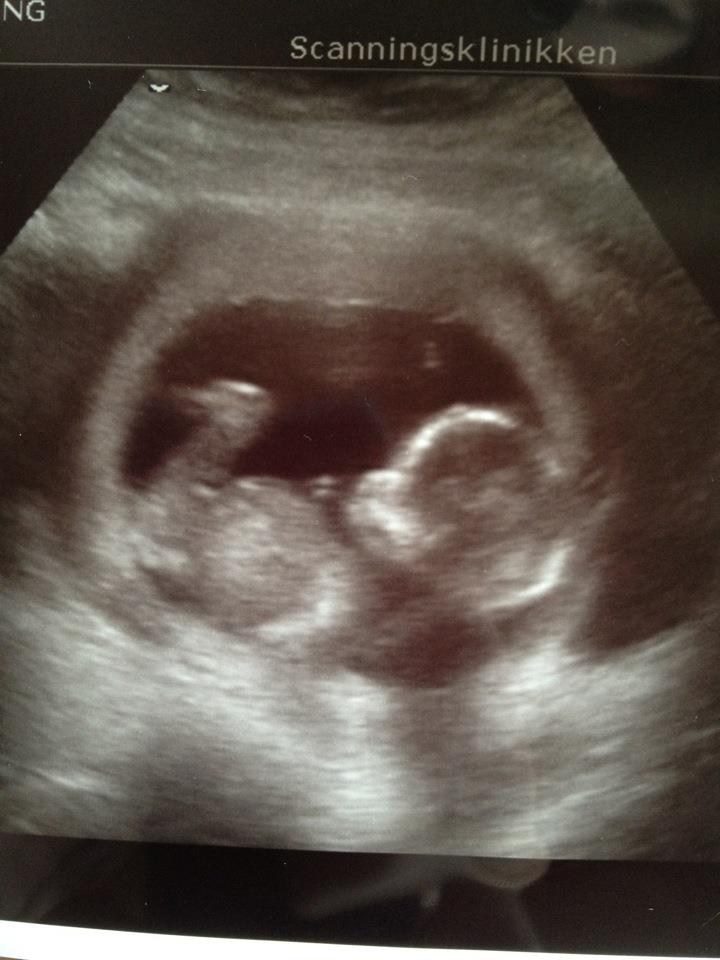

I maven gemmer der sig en lille PRINSESSE hehe

Hun er nu 17 cm lang og vejer 150 g

men hun var nu ikke meget for at vise sit køn haha.. hun lå bare med benene samlet og med navlestrengen lige imellem så ih hvor var det svært at se men efter en del hopperi så kunne vi  tydligt se en dejlig lille pige